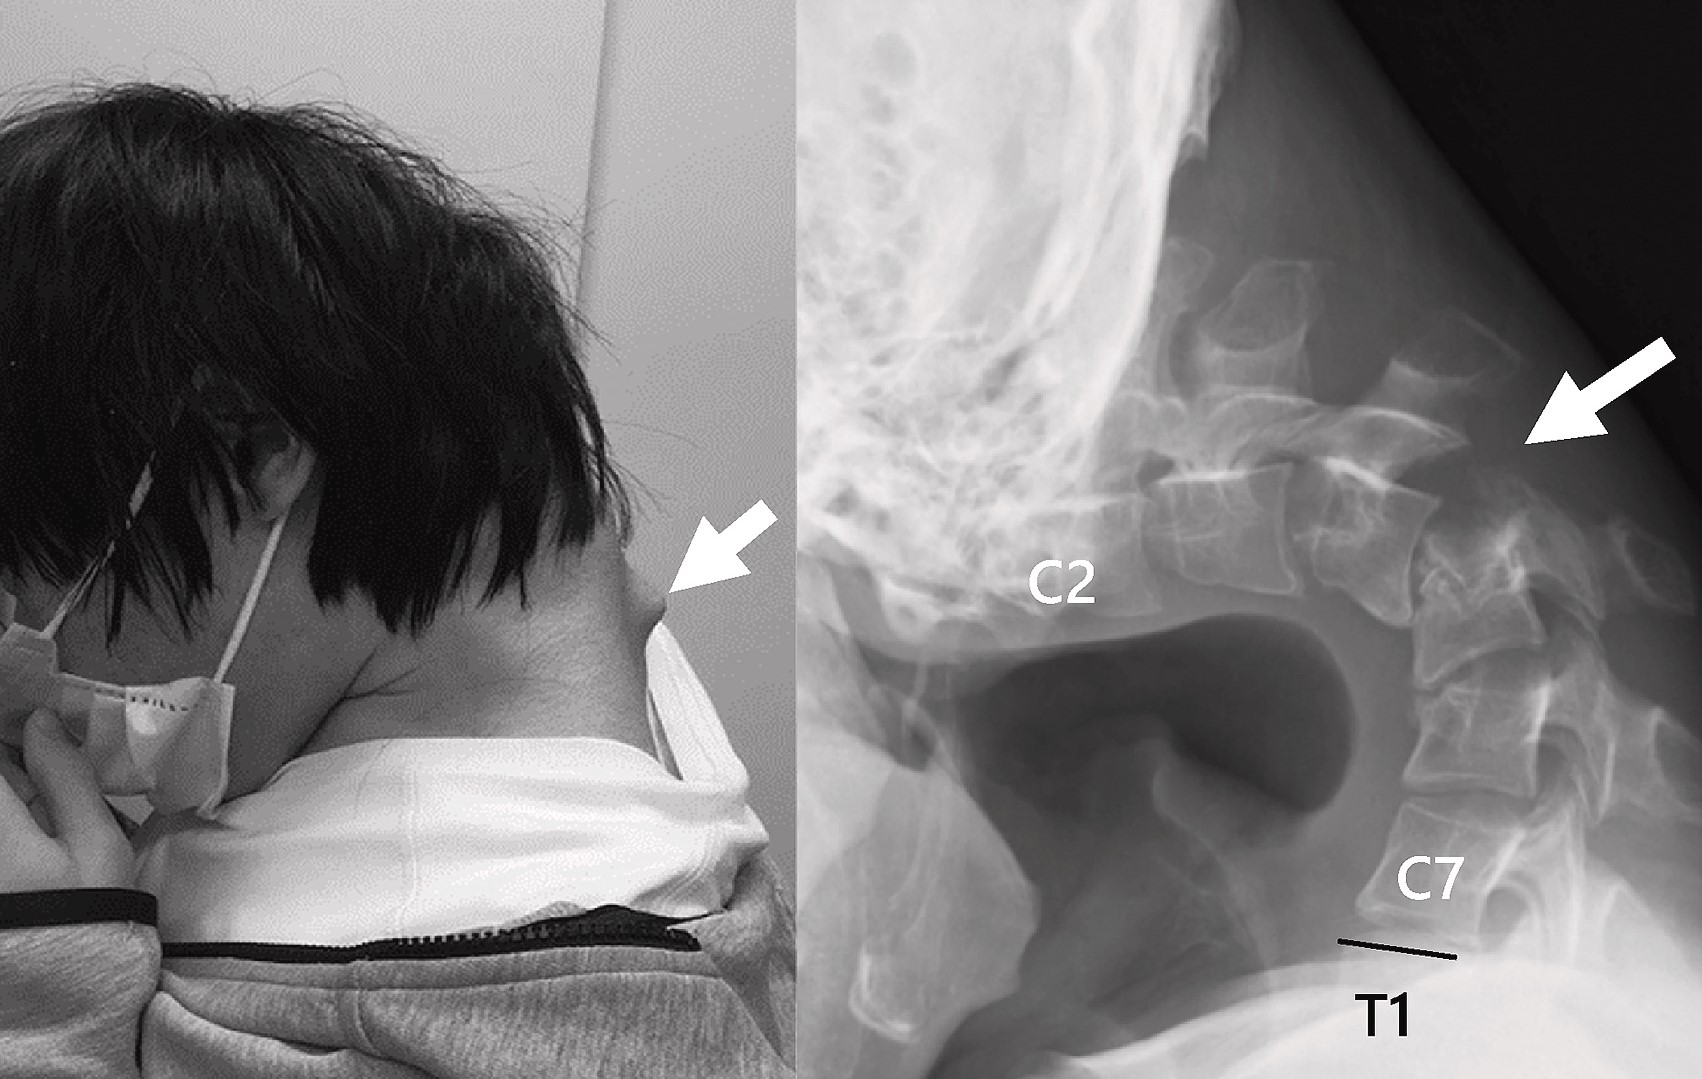

Pacientu, ki je ure in ure preživljal ob igranju igric na pametnem telefonu, se je na zatilju pojavila izrazita izboklina in sčasoma je izgubil sposobnost dviga glave z lastnimi vratnimi mišicami.

Zaradi tega je opustil šolanje in začel večino dni preživljati sam, zaprt v sobi, ob telefonu. Dolgotrajno sklanjanje nad zaslonom je povzročilo deformacijo hrbtenice in nastanek večje izbokline na vratu.

Slikanje je pokazalo, da so se vretenca v vratu izkrivila in premaknila, na zgornjem delu hrbtenice pa se je zaradi dolgotrajne ekstremne raztegnjenosti oblikovalo brazgotinsko tkivo.